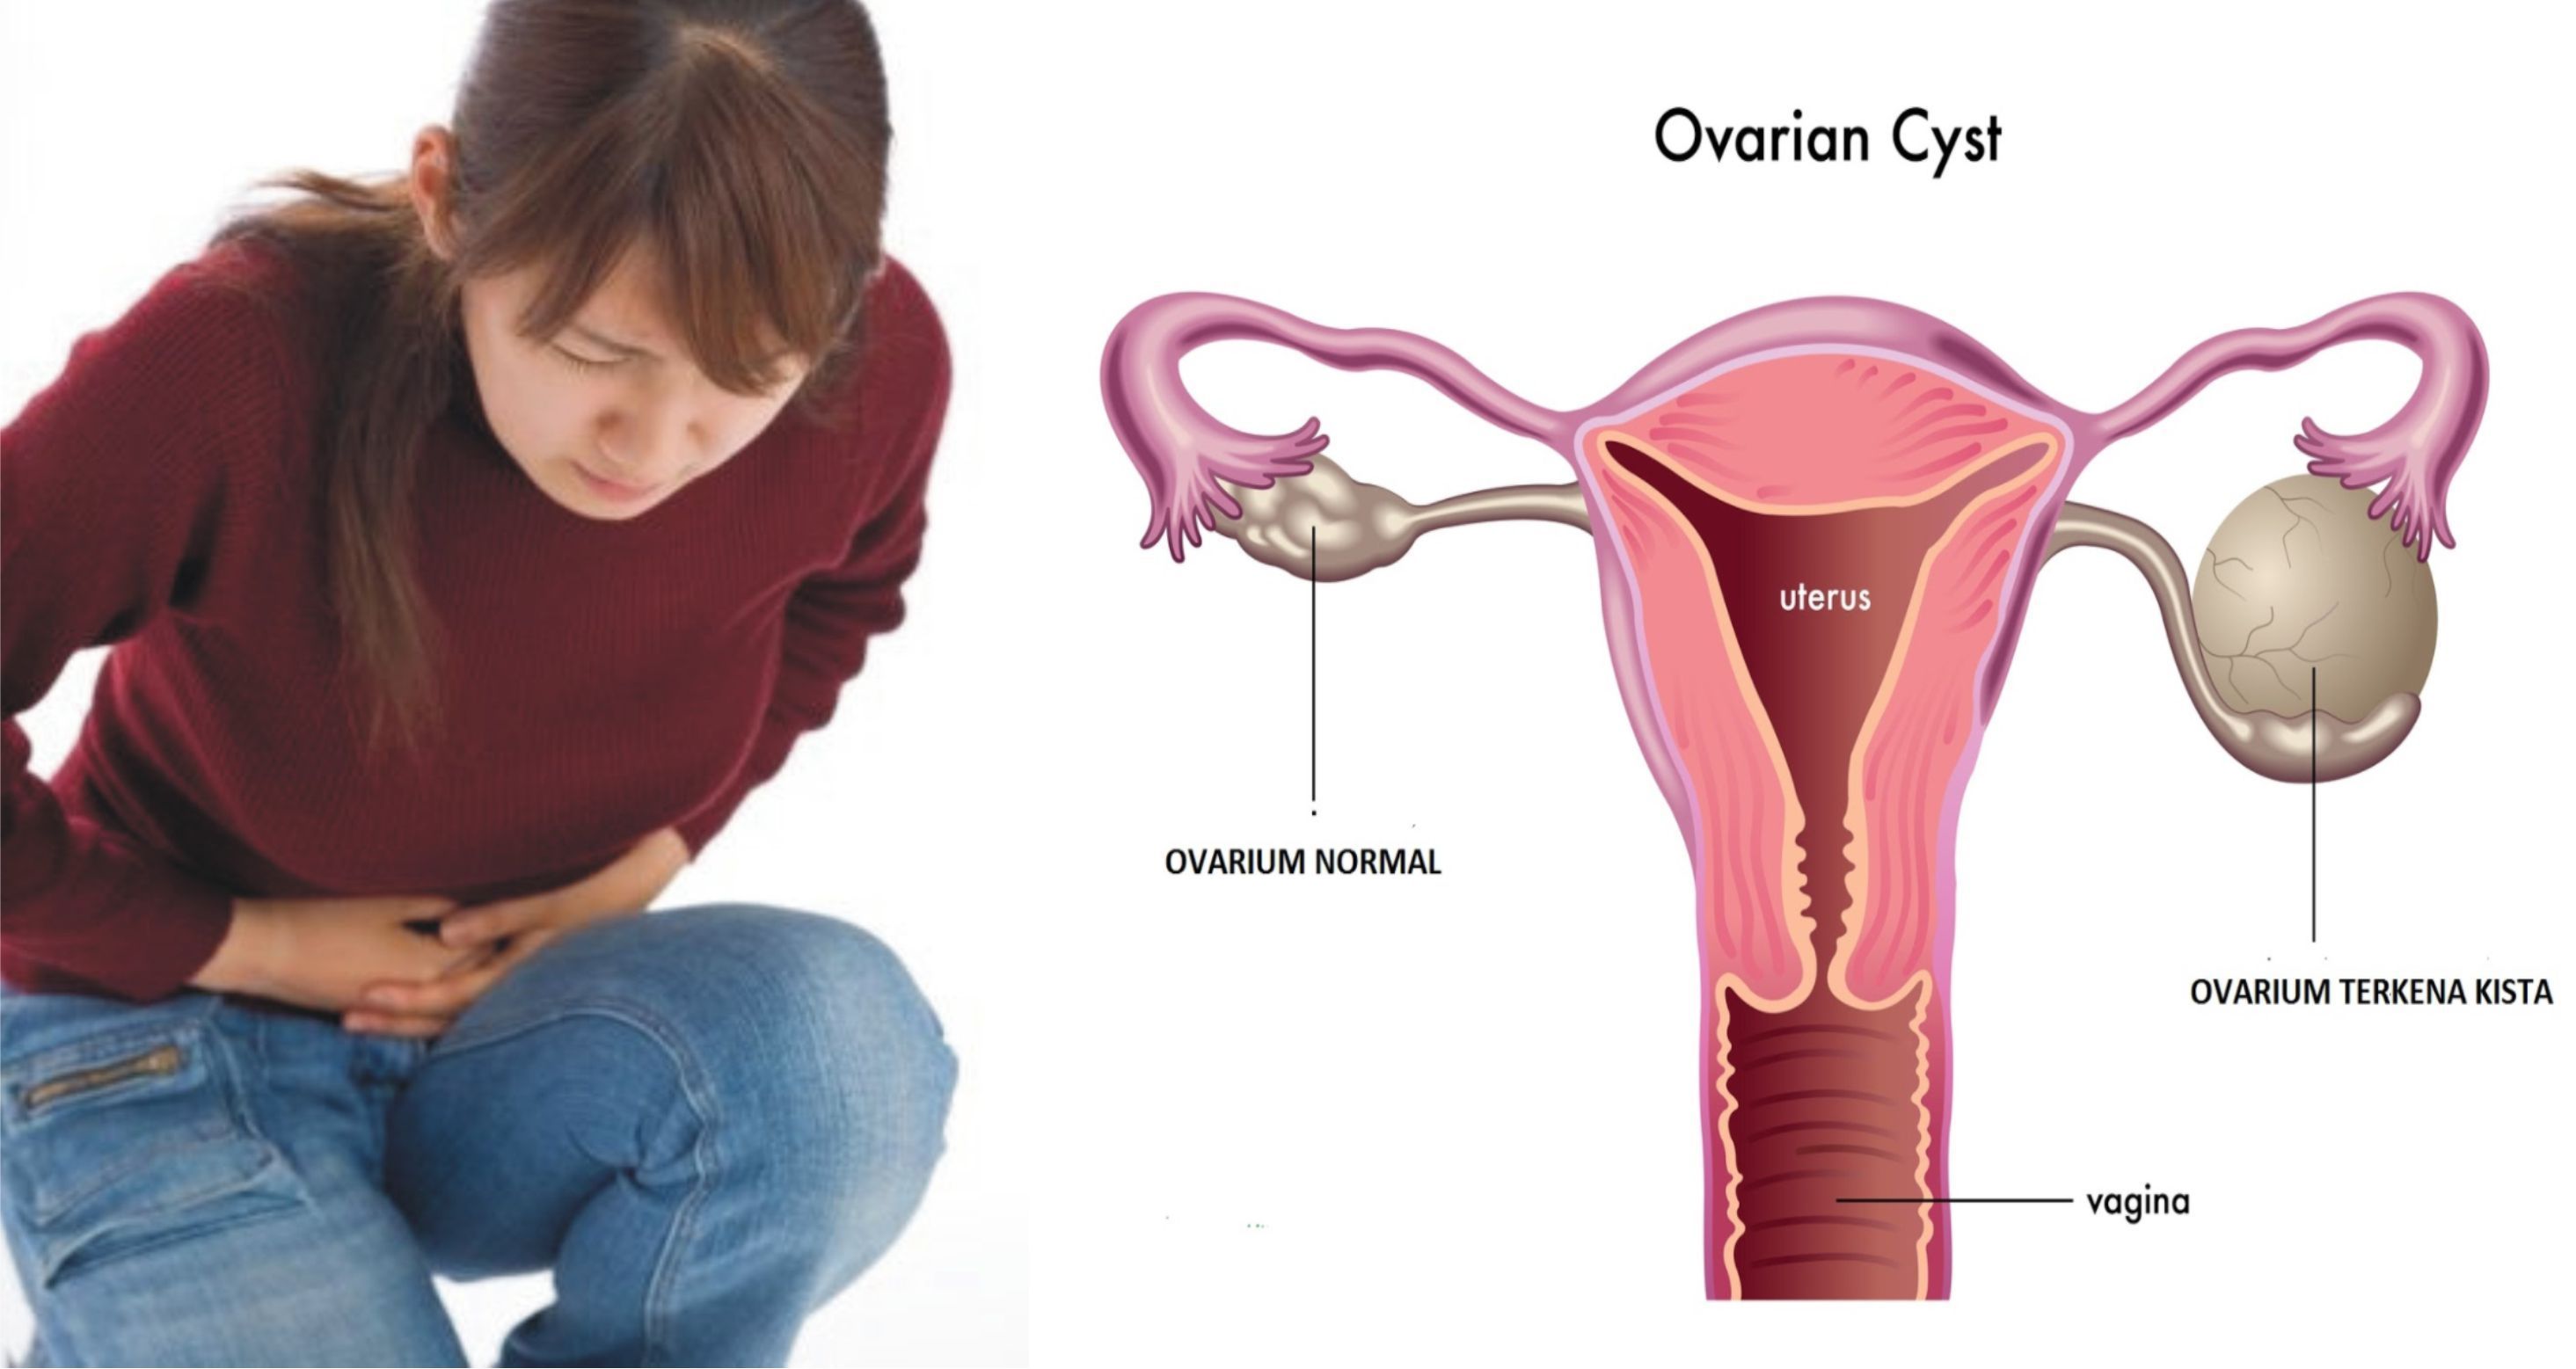

Bahaya kista: Bahaya Kista Ovarium

Bahaya kista: Bahaya Kista Ovarium